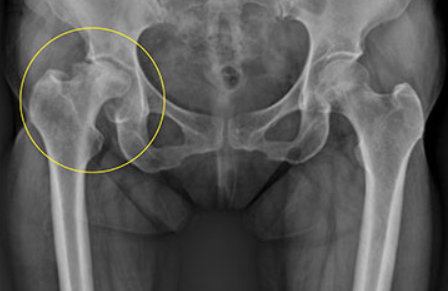

대퇴골두 무혈성괴사

쉽게 말해서 고관절 근처의 혈액순환에 문제가 생겨서 대퇴골 머리 부분에 혈액이 제대로 공급되지않게 됩니다. 이럴 경우 혈액이 공급되지 않아 뼈가 썩게 됩니다.